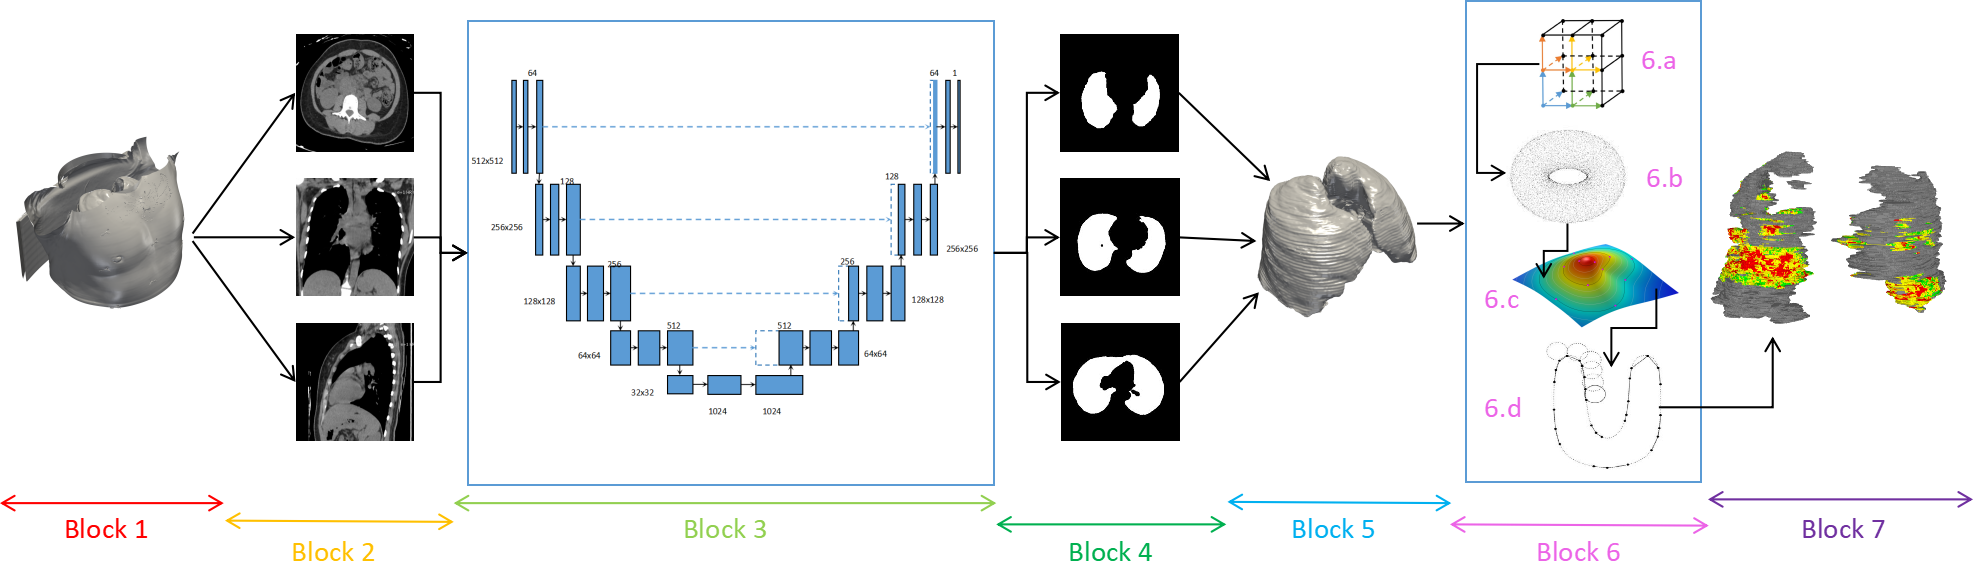

We present TARU-Net, a unified framework that fuses deep learning-based segmentation with surface topology-guided 3D reconstruction. The architecture captures rich multi-scale spatial features, ensuring resilient performance even in complex pathological landscapes such as fibrosis, tumors, or pneumonia. The subsequent topology-driven reconstruction, implemented via the Marching Cubes algorithm with RBF interpolation and Ball Pivot Algorithm, smoothens jagged voxel artifacts and restores anatomical realism, producing seamless, high-fidelity 3D lung models directly from patient CT data.

TARU-Net integrates three key stages: (1) U-Net-based 2D CT slice segmentation for lung and lesion extraction, (2) 3D surface reconstruction using Marching Cubes followed by RBF interpolation for smooth, gap-free surfaces, and (3) Ball Pivot Algorithm for watertight mesh generation with color-coded severity mapping based on Hounsfield Units.

We present a unified computational pipeline that seamlessly integrates 2D deep learning-based segmentation with 3D surface topology-driven reconstruction for volume visualization, generating anatomically faithful, color-coded models of the human lung. By leveraging U-Net's feature-extraction capabilities coupled with topology-based surface reconstruction, TARU-Net achieves high accuracy in delineating lung parenchyma, airways, and pathological regions.

The fusion of deep learning and topology-aware reconstruction transforms discrete CT voxel data into realistic 3D representations with smooth, anatomically consistent surfaces. This hybrid approach surpasses traditional methods in robustness, adaptability to diseased tissues (fibrotic or tumorous lungs), and computational efficiency—offering transformative potential for diagnosis, surgical planning, computational medicine, and medical education.